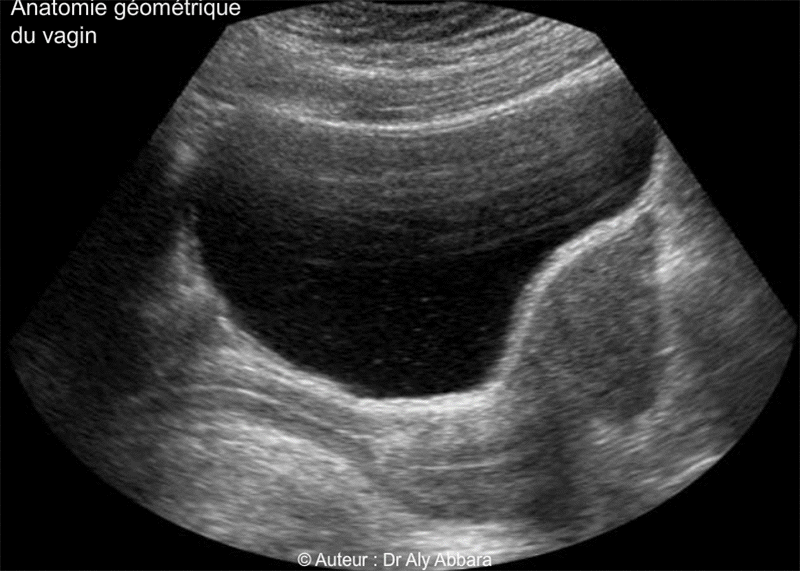

Vagin de femme adulte - Rapports anatomiques - Echographie

(Coupe échographique sagittale médiane du pelvis - vessie pleine).

Le vagin est situé dans la cavité pelvienne, entre la vessie et l'urètre en avant et le rectum en arrière ; il se fixe en haut sur le col utérin (عنق الرحم) qui fait saillie dans sa cavité mais les parois vaginales restent séparées du col utérin par un cul-de-sac (رتج) annulaire (ou fornix vaginal) divisé en quatre segments (deux culs-de-sacs latéraux, droit et gauche; un cul-de-sac antérieur et un cul-de-sac postérieur).

• Morphologiquement le vagin est plus étroit au niveau de son tiers inférieur, près de la vulve, puis il s'élargit au niveau de son tiers moyen et surtout au tiers supérieur, cette étroitesse relative dans la portion vaginale située près de son entrée vulvaire est due à la présence des fuseaux musculaires des muscles releveurs de l'anus qui encerclent cette partie du vagin en arrière et bilatéralement. Cet encerclement musculaire donne au vagin une forme coudée, donc en position allongée, sur un plan sagittal médian, la partie basse du vagin est oblique (de l'arrière en bas vers l'avant en haut), la partie haute du vagin se dirige vers l'arrière. L'angle formé par les deux axes du vagin est un angle obtus, ouvert vers le bas (en position allongée) et sa valeur est égale à environ à 140 degrés.

L'orifice externe du col utérin est posé sur la paroi postérieure du fond du vagin car l'axe du col est presque vertical sur la paroi vaginale postérieure.